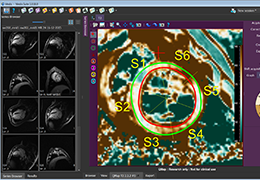

View X-Ray CT & MRI Scans Fast and Easily

Designed for surgeons, Pro Surgical 3D makes it easy to view patient scans quickly. Pro Surgical 3D facilitates the optimal 3D treatment and assessment workflows based on X-ray CT and MRI scans – and best of all, it’s FREE!

High-quality and fast 3D reconstruction and 3D rendering

Performs 3D reconstruction and volume rendering.

Multi-planar slicing.

Oblique slicing.